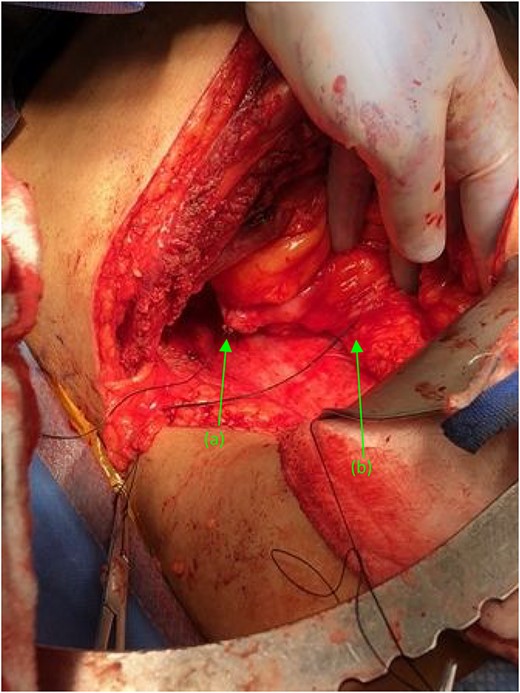

Attention was turned back to the fistulous connections at their duodenal entry points (Fig. 4). Both fistulas, were trimmed to their base, debrided, and primarily closed using 3-0 Vicryl sutures in an interrupted fashion. Interrupted 3-0 Vicryl sutures were then used to Lambert the repaired 2nd and 3rd portions of the duodenum (Fig. 5). Acti-seal sealant was sprayed atop the repairs, and Gerota’s was laid atop. Surgicel was then placed in the raw, inflamed posterior space of the fossa and adequate hemostasis was achieved. A 19 French Blake drain was brought through an inferior skin incision, laid in the renal fossa adjacent to the duodenal repairs, and sutured in place. The abdomen was then closed in the standard fashion, with individual suture closure of the fascia, internal and external oblique muscles and skin layers.

Two suture tagged fistulas status post fistulectomy and debridement to their base, entering the (a) second and (b) third portions of the duodenum, status post nephrectomy.

(a) Repaired duodenal defect where the (first) fistula previously entered the second portion of the duodenum, status post fistulectomy and stump closure. (b) Second fistula indicated by suture tags status fistulectomy and trimming to the base of the fistulous tract, near its entry point at the third portion of the duodenum.